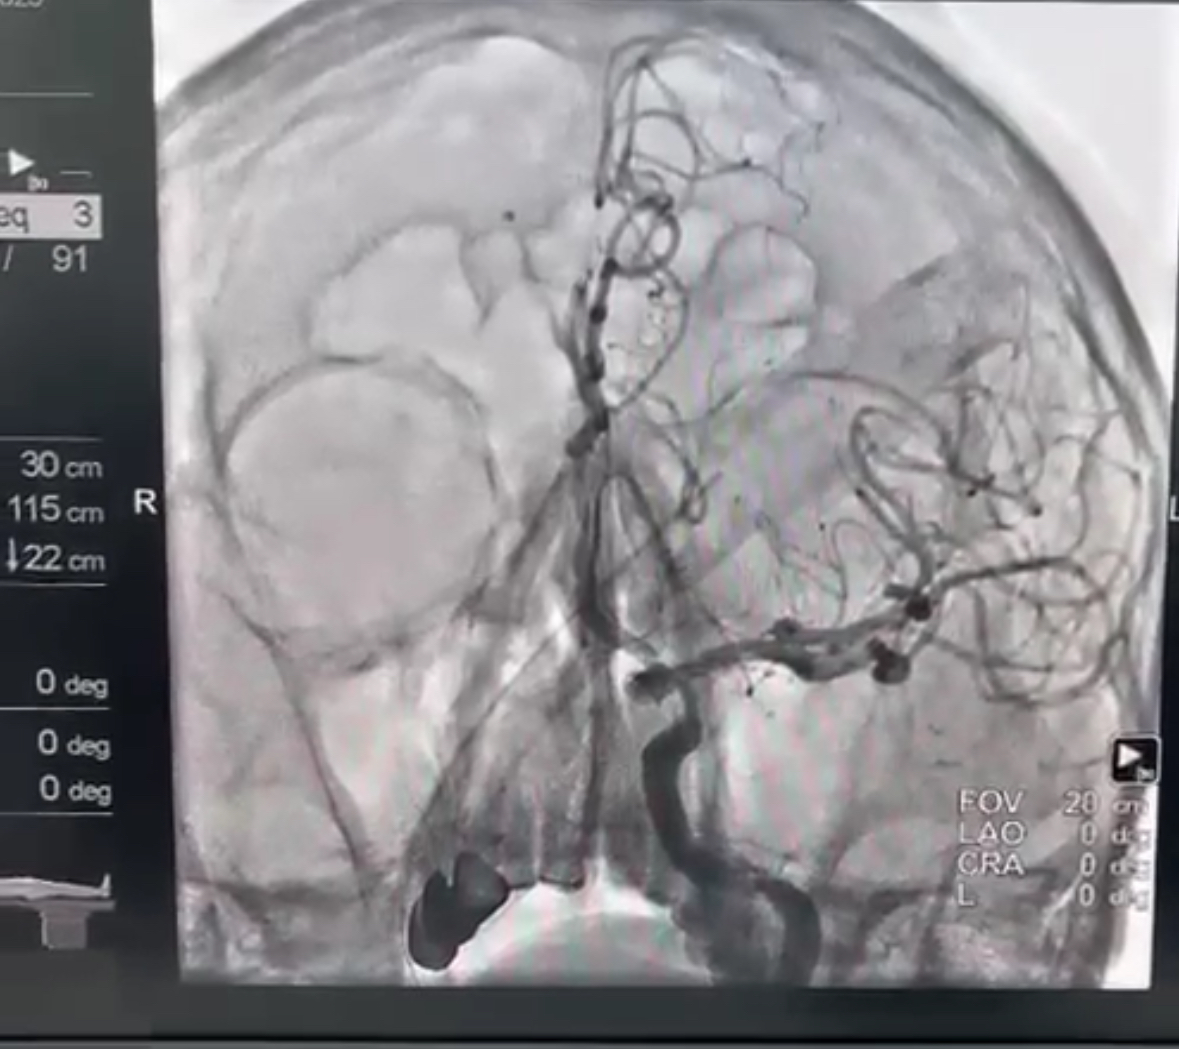

Спустя двое суток пациента постигла новая беда – ишемический инсульт. Благодаря оперативному вмешательству эндоваскулярного хирурга тромб был успешно удален, предотвратив тяжелые последствия для головного мозга.